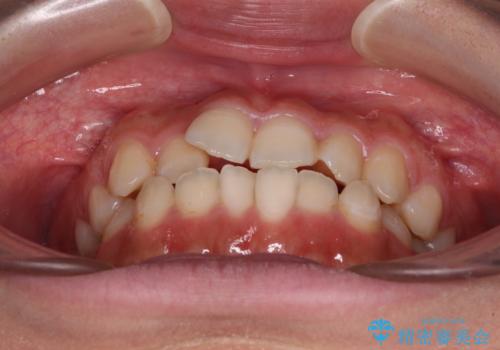

- 前歯のデコボコを気にして来院された患者様です。

マウスピース矯正のような自己管理の煩わしさがなく、早く治療を終えたいとのことで、ワイヤー装置による矯正治療を行うこととしました。